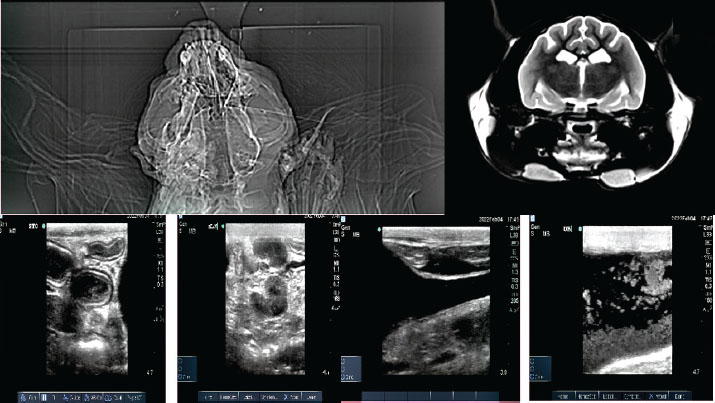

Symptomatic treatment, including fluid therapy and antimicrobial coverage (intramuscular gentamicin sulfate at 15,000 IU), led to the resolution of gastrointestinal signs within 1 week. However, the animal developed persistent anorexia, progressive weight loss, lethargy, and mild ataxia. Chemical immobilization was performed on day 10 post-admission to facilitate advanced diagnostics. Blood samples were collected for serum protein electrophoresis, conventional polymerase chain reaction, and Reverse Transcription Polymerase Chain Reaction (RT-PCR) targeting feline coronavirus (FCoV) (Simons et al., 2005; Wang et al., 2021; Gao et al., 2022) (Supplementary Material S2). Molecular diagnostics confirmed the presence of FCoV RNA in blood samples (Tables 3, 5, and 6 for detailed results and primer sequences; primers were designed based on previously published sequences (Hohdatsu et al., 1991; Stranieri et al., 2020,Böger et al., 2021; Lin et al., 2022). The reference strains included FIPV WSU-79-1146, type II 79-1683, UCD2, UCD4, and FECV UCD (Table 4). Abdominal ultrasonography revealed decreased hepatic echogenicity with possible hepatomegaly, splenomegaly, hyperechoic mesenteric fat, and enlarged mesenteric and sublumbar lymph nodes. Mild abdominal effusion was also noted (Fig. 2B,C). Brain CT showed enhanced meningeal layers and choroid plexus of the fourth ventricle, suggesting meningeal inflammation (Fig. 2A). immunohistochemistry (IHC) and ISH were performed on formalin-fixed paraffin-embedded tissues using established protocols (Stranieri et al., 2020) (Supplementary Material S3). Briefly, IHC employed monoclonal anti-CD68 antibody (1:50; clone KP1, Dako, Denmark) for macrophage identification, anti-cleaved caspase-3 (1:60; Cell Signaling Technology, USA) for apoptosis detection, and broadly cross-reactive anti-ACE2 antibody (1:500; Abcam, UK) for receptor expression (Junqueira et al., 2022). ISH was performed using RNAscope technology (ACD/Bio-Techne, USA) with FIPV-specific spike gene probes (Tortorici et al., 2021; Takeda, 2022; Tortorici et al., 2022). IHC confirmed the presence of FCoV antigen in macrophages within granulomatous lesions, and ISH localized viral RNA to inflammatory foci (Table 7, Fig. 1B,C).

Fig. 2. Diagnostic imaging findings. (A) Brain computed tomography with enhanced meninges and choroid plexus. (B) Abdominal ultrasound showing hepatomegaly, splenomegaly, and enlarged mesenteric lymph nodes. (C) Sediment in the urinary bladder and mild abdominal effusion.